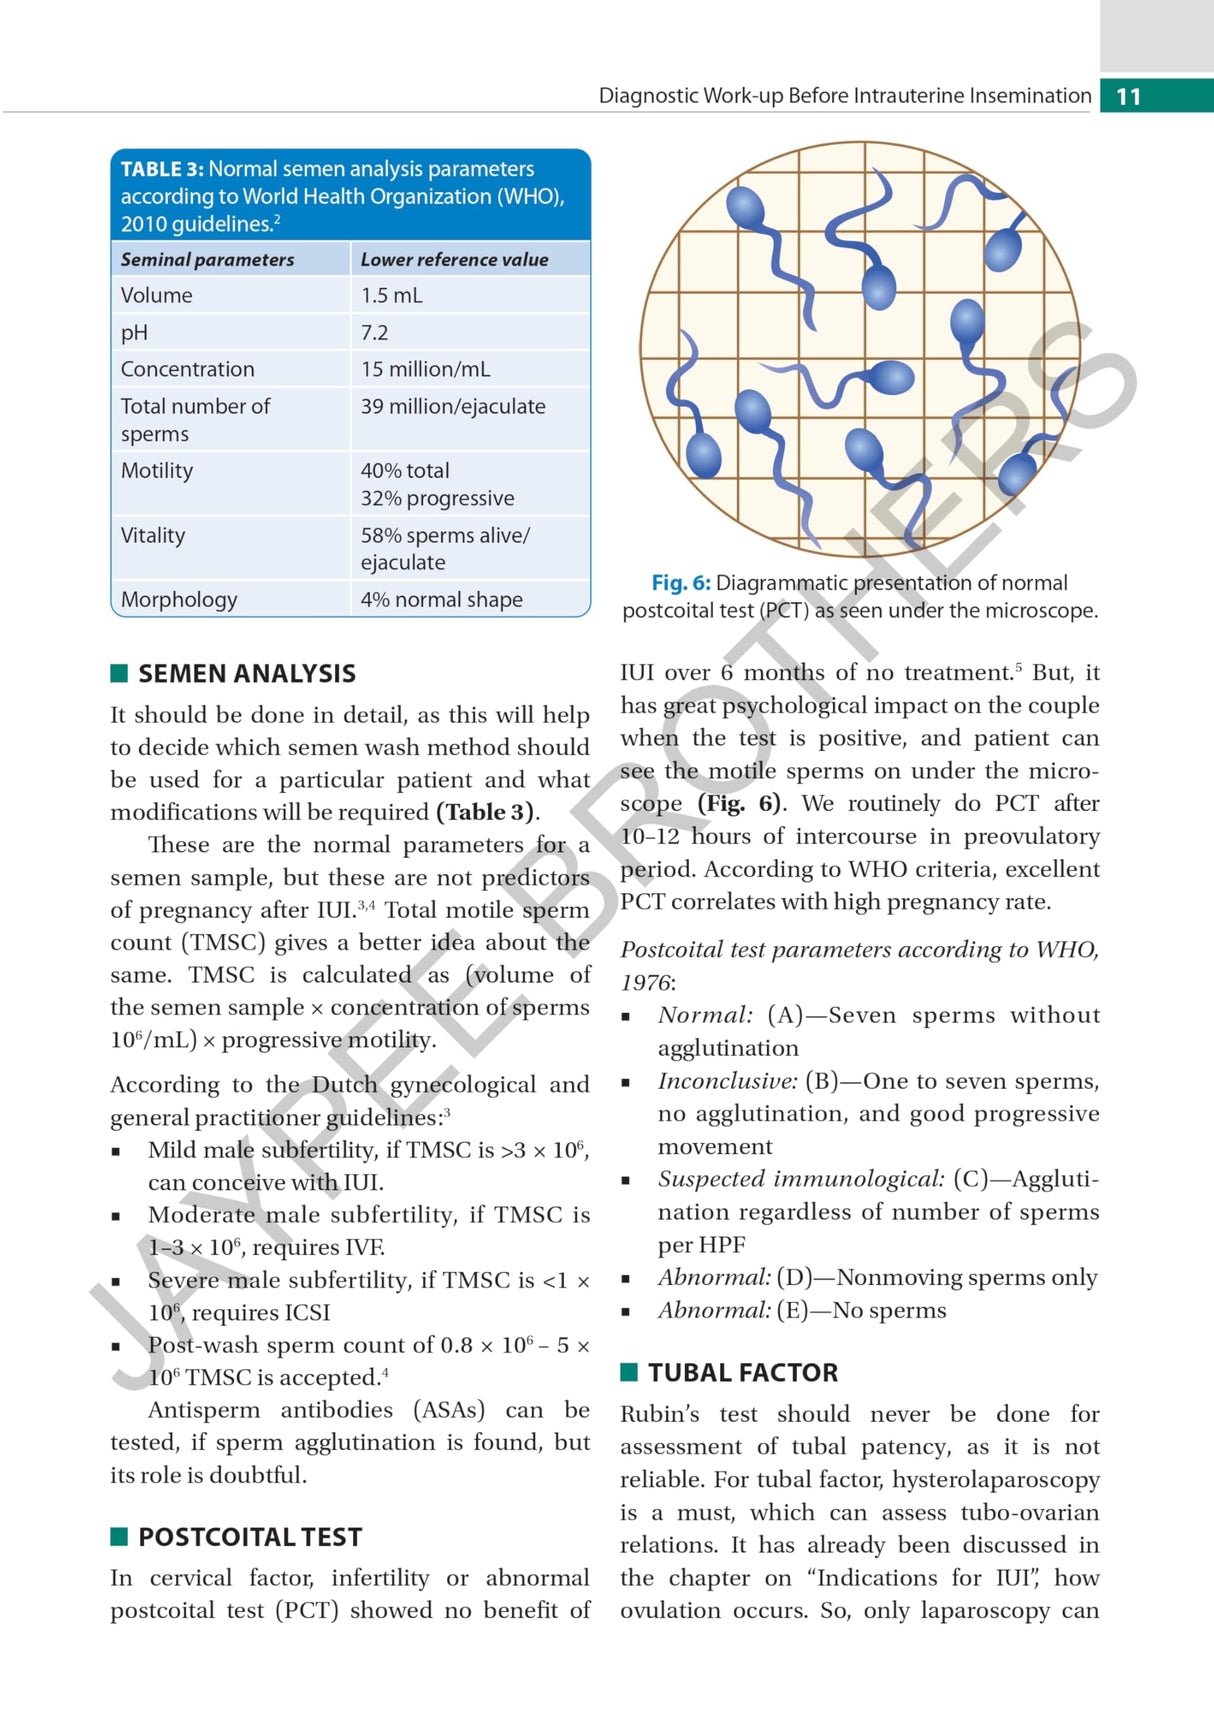

Beginning with discussion on counselling and diagnostic work-up before IUI, the next chapters cover indications and ultrasound. The following sections examine ovulation, timing of IUI, techniques, luteal phase support, complications, and factors affecting success. The final chapter discusses sperm preparation.

The text is further enhanced by clinical images and figures.